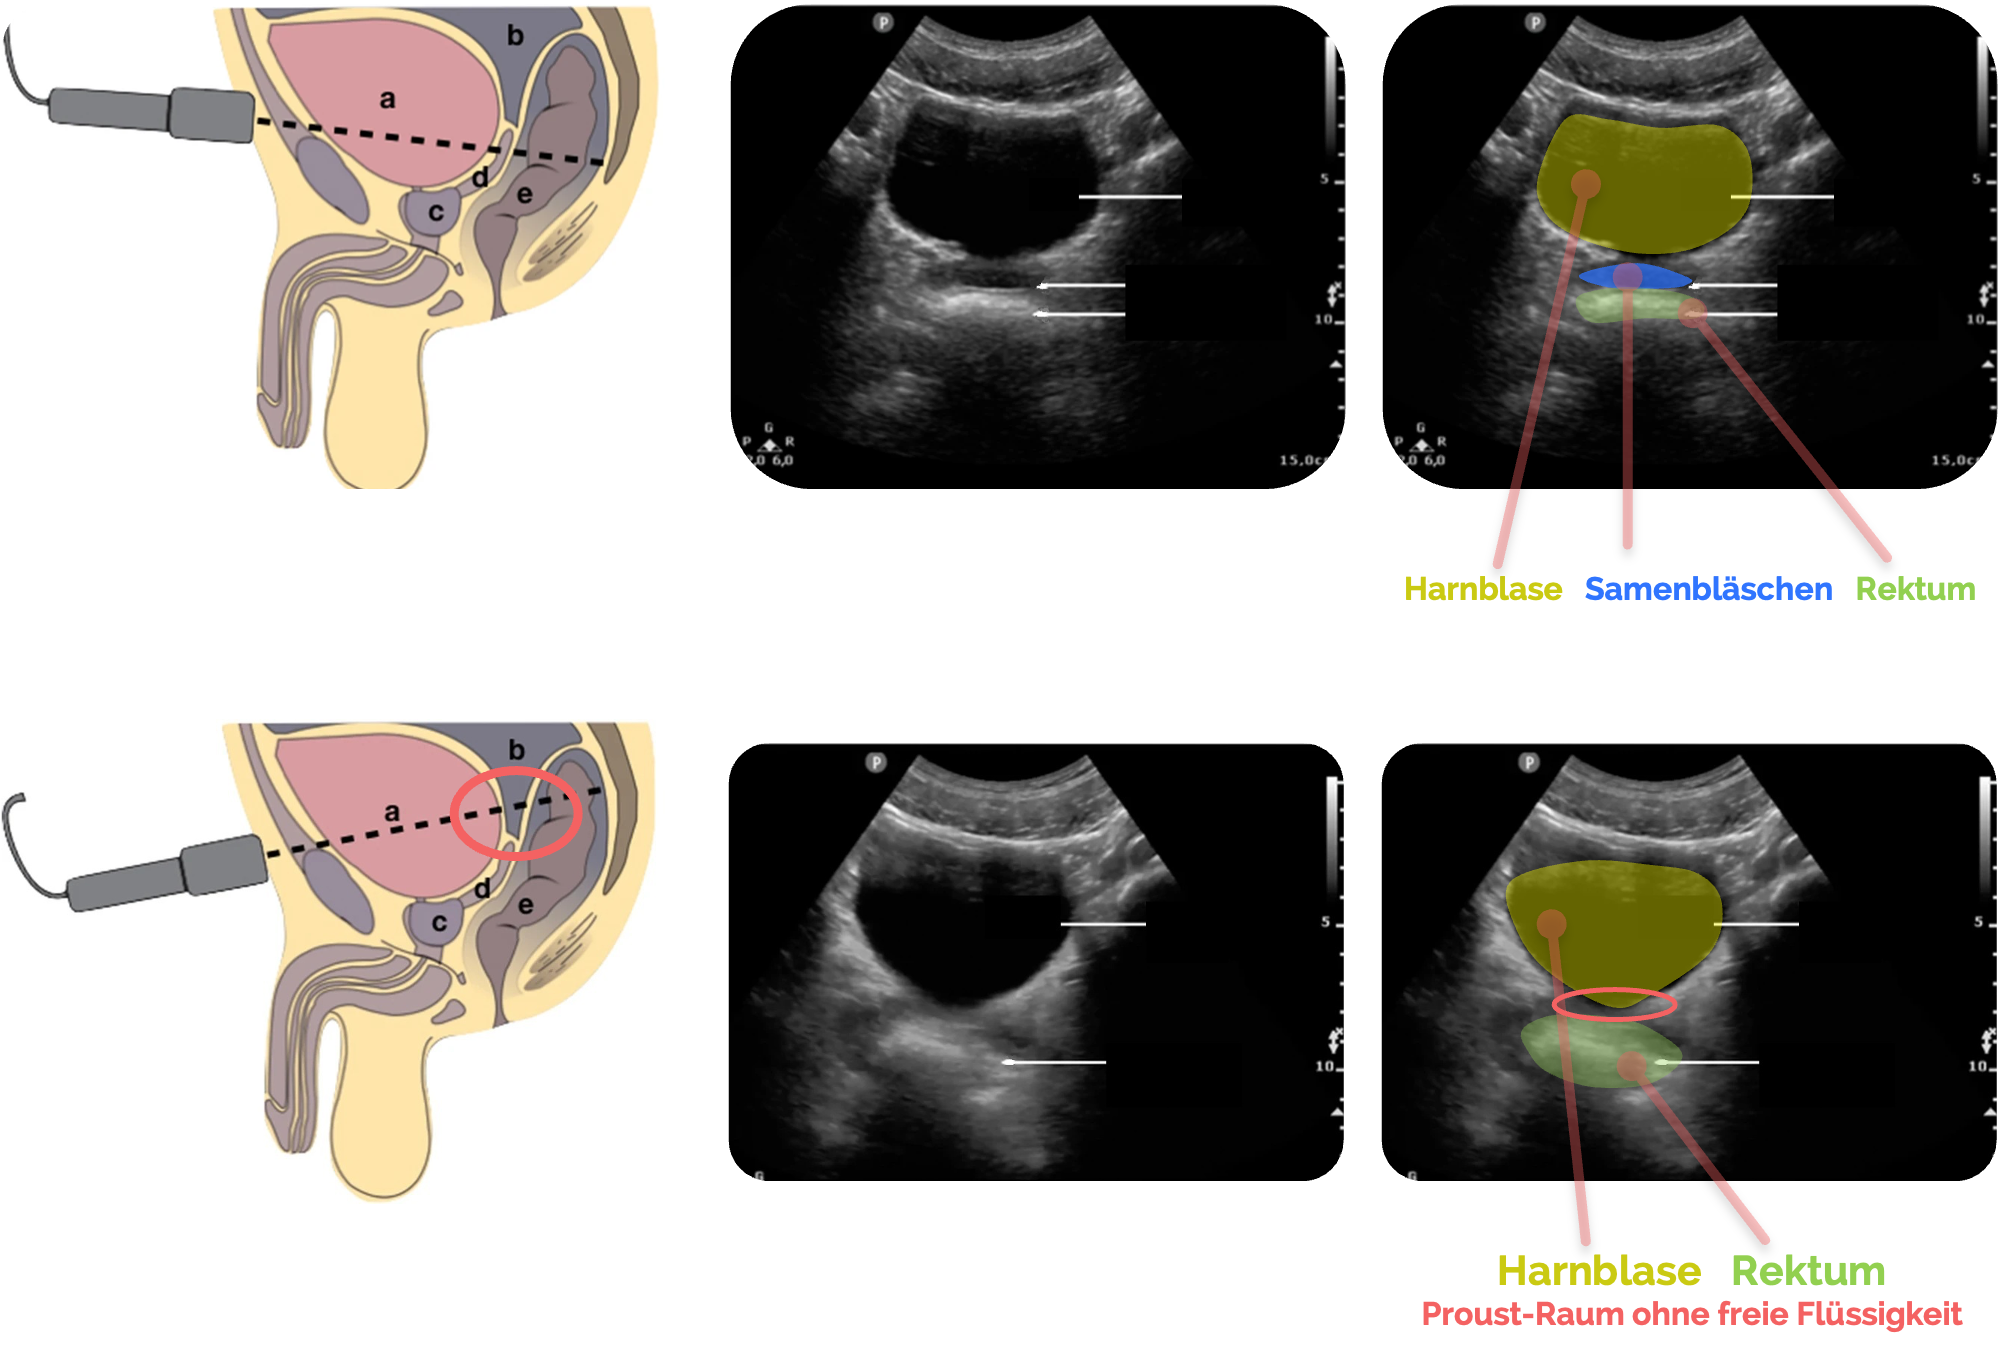

Orientierung beim Mann:

- Harnblase ebenfalls als Fenster

- Rektovesikaler Raum direkt dorsal der Blase

(siehe roter Pfeil) - Rektum

AchtungWird die Sonde zu weit nach kaudal gekippt, können die Samenbläschen mit freier Flüssigkeit verwechselt werden! (siehe folgende Abschnitte)

Figure 2 aus Fasseaux, A., Pès, P., Steenebruggen, F. et al. Are seminal vesicles a potential pitfall during pelvic exploration using point-of-care ultrasound (POCUS)?. Ultrasound J 13, 14 (2021). https://doi.org/10.1186/s13089-021-00209-7. Es wurden der rote Pfeil und die Beschriftungen hinzugefügt.

Normalbefund beim Mann

Im Normalbefund zeigt sich der Proust-Raum als ein schmaler, echoarmer Spaltraum zwischen Harnblase und Rektum

Die Harnblase erscheint anterokaudal als glatt begrenzte, echoarme Struktur, während das Rektum

AchtungWird die Sonde zu weit nach kaudal gekippt, können die Samenbläschen mit freier Flüssigkeit verwechselt werden!

Figure 2 aus Fasseaux, A., Pès, P., Steenebruggen, F. et al. Are seminal vesicles a potential pitfall during pelvic exploration using point-of-care ultrasound (POCUS)?. Ultrasound J 13, 14 (2021). https://doi.org/10.1186/s13089-021-00209-7. Die Bilder wurden zugeschnitten. Es wurden teilweise die Markierungen und Beschriftungen ergänzt.

a: Blase

Die Samenbläschen stellen sich in der Regel als symmetrische, scharf begrenzte ovale Strukturen dar. Die Lage direkt oberhalb der Prostata ist ein wichtiges Unterscheidungskriterium gegenüber freier Flüssigkeit, die hier in der Regel nicht vorkommt.

Zur besseren Unterscheidung ist die longitudinale Achse sehr hilfreich. Insbesondere, wenn eine unzureichende Blasenfüllung vorliegt, kann man in dieser Schnittebene Harnblase und Rektum